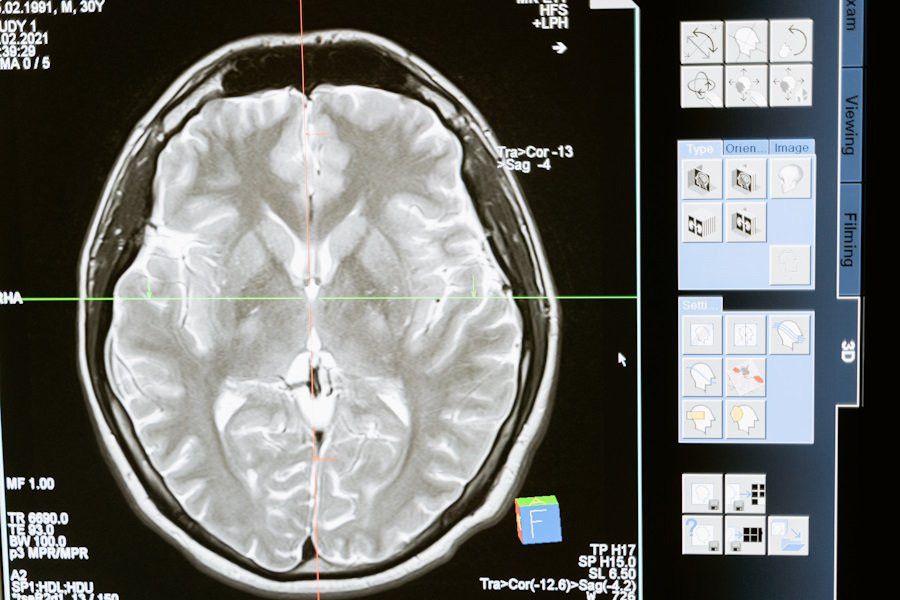

Наш мозг активно генерирует электрические сигналы в различных ситуациях, будь то физическая активность, еда или отдых. В состоянии покоя, когда мы думаем или просто расслабляемся, преобладают альфа-колебания на частоте 8–12 Гц. У пациентов с депрессией часто наблюдается нарушение равновесия этих альфа-волны в префронтальной коре, особенно в левой части.

Для решения этой проблемы учёные разработали замкнутую систему, способную измерять индивидуальные альфа-частоты и стимулировать мозг слабым переменным электрическим током. Этот метод направлен на восстановление нормального баланса альфа-колебаний.